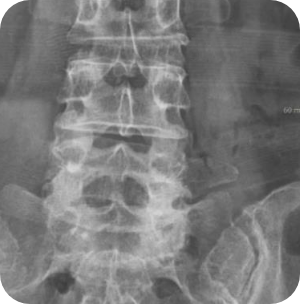

- 극외측협착증

- 척추분리증성 전방전위증